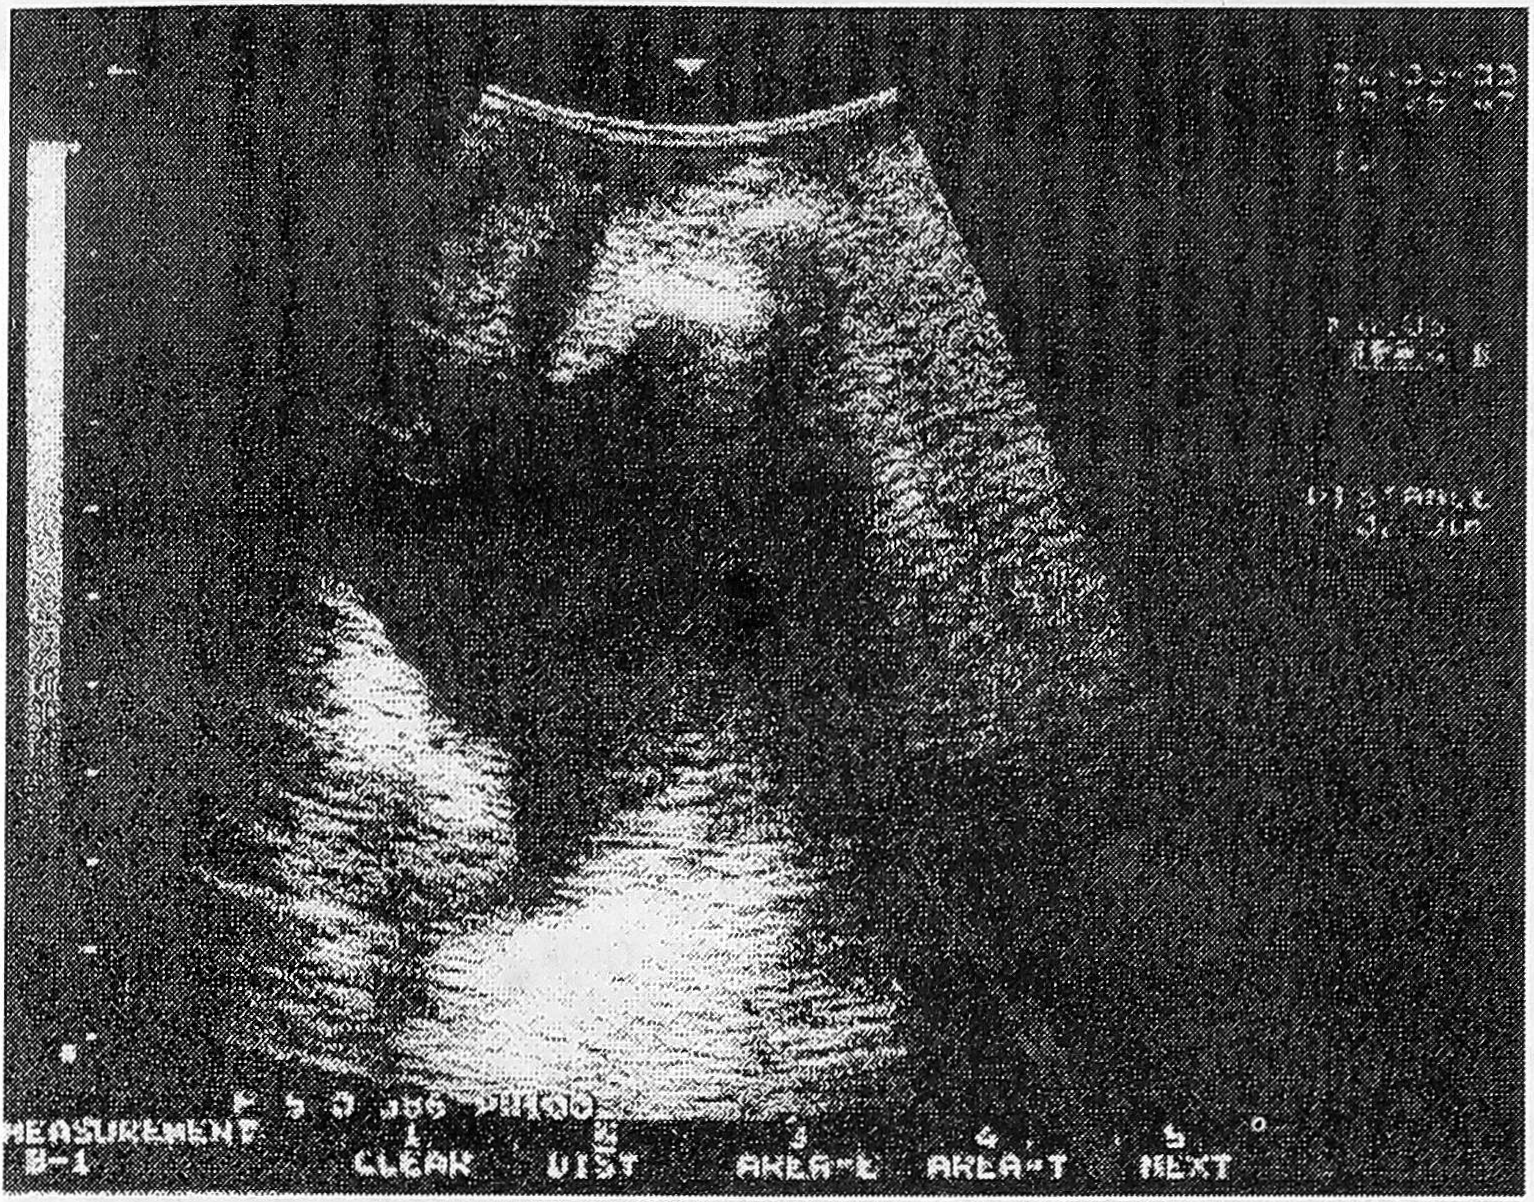

В результате ультразвукового сканирования у 25 женщин с уретритом получены следующие данные: позыв на мочеиспускание у всех женщин появился при ретроградном заполнении мочевого пузыря теплым раствором фурациллина в количестве от 50 до 150 мл (в среднем 98,8 мл), при этом длина уретры (при трансвагинальном сканировании) варьировала от 2,0 до 3,2 см (в среднем 2,57 см), ширина составляла от 0,3 до 1,0 см (в среднем 0,67 см). Форма уретры была разной: овальная у 16 (64,0% ±12,0) женщин, воронкообразная у 6 (24,0% ±17,4), колбообразная у трех (12,0%±18,7) (рис. 1, 2, 3). При стандартном заполнении мочевого пузыря (150-250 мл) образование цистоуретральной воронки наблюдалось у двух (8,0%±19,1) женщин, при этом отмечено укорочение уретры на 0,2-0,5 см (в среднем на 0,32 см), что находится в рамках физиологических колебаний. Проба Маршала во всех наблюдениях была отрицательной, т.е. недержания мочи при заполнении мочевого пузыря не было у всех пациенток. Остаточная моча в количестве 30,0 мл определялась лишь у одной пациентки, у которой помимо признаков уретрита имел место и острый цистит, эхографически видный как утолщение стенок мочевого пузыря и яркого свечения полости слизистой мочевого пузыря (рис. 4).

Рис. 3. УЗ-сканирование уретры у женщины с уретритом (колбообразная уретра).